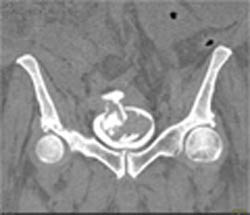

Diagnosis

Stent in LAD